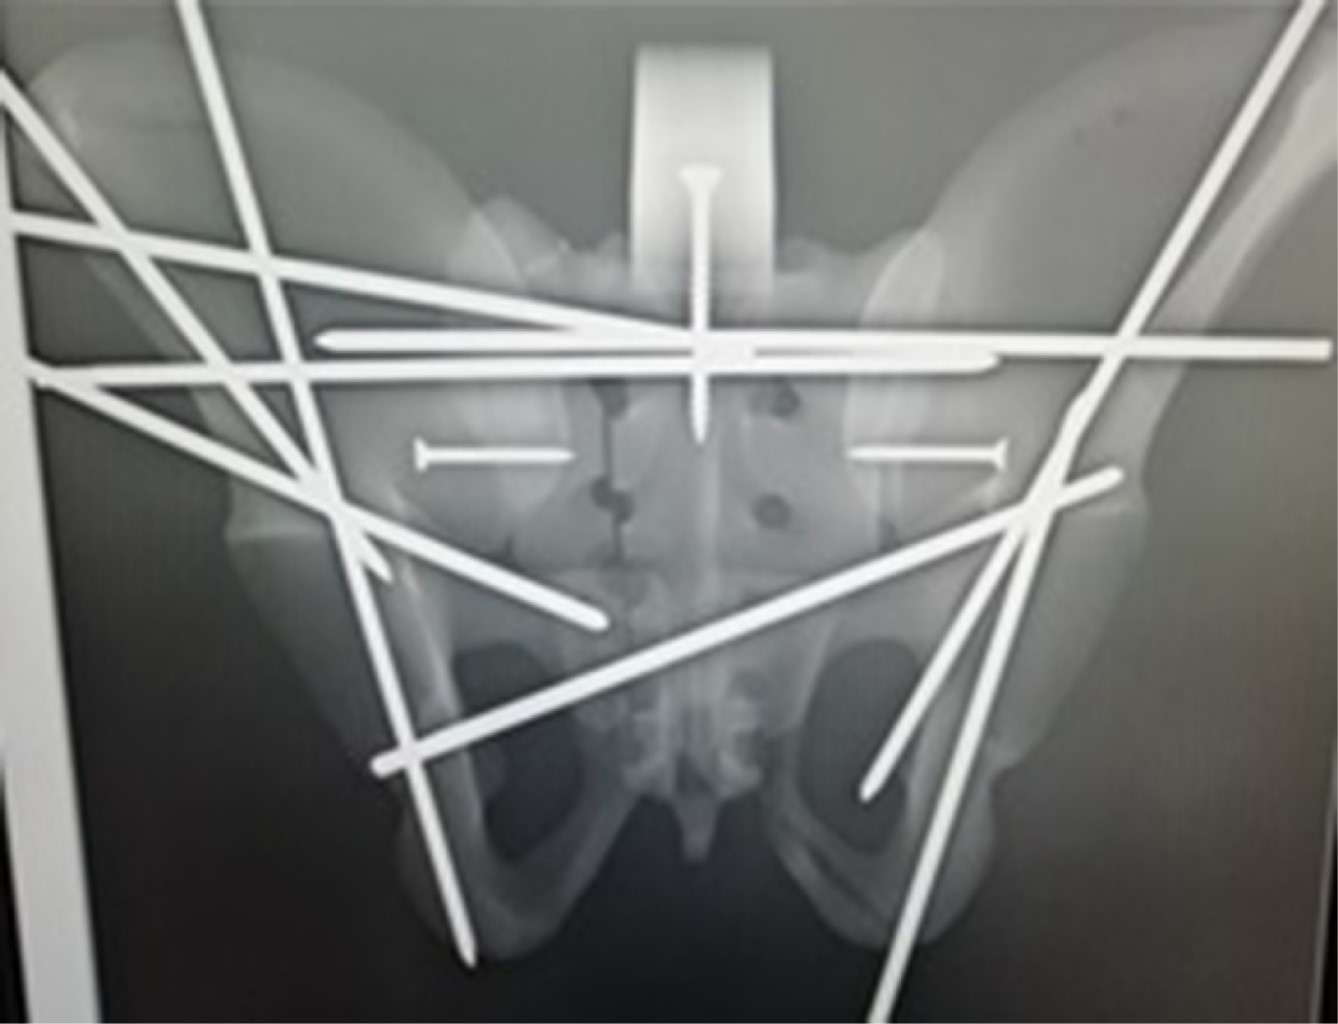

Las complicaciones de la fijación pélvica percutánea son variadas y se dividen en errores relacionados con el cirujano, la técnica y el paciente.6 El tratamiento percutáneo de las lesiones del anillo pélvico inestable es un procedimiento técnicamente exigente con una curva de aprendizaje pronunciada (Figura 4). Una comprensión profunda de la anatomía pélvica, vascular y neurológica es vital para prevenir complicaciones graves. La colocación percutánea de los tornillos en fracturas de pelvis y acetábulo puede presentar complicaciones como el mal posicionamiento de los tornillos, mala reducción de la fractura, infección, riesgo de daño neurológico, vascular y estabilidad insuficiente, lo que puede provocar no unión o desanclaje del material de osteosíntesis y asociarse con cirugías de revisión.8

Figura 4